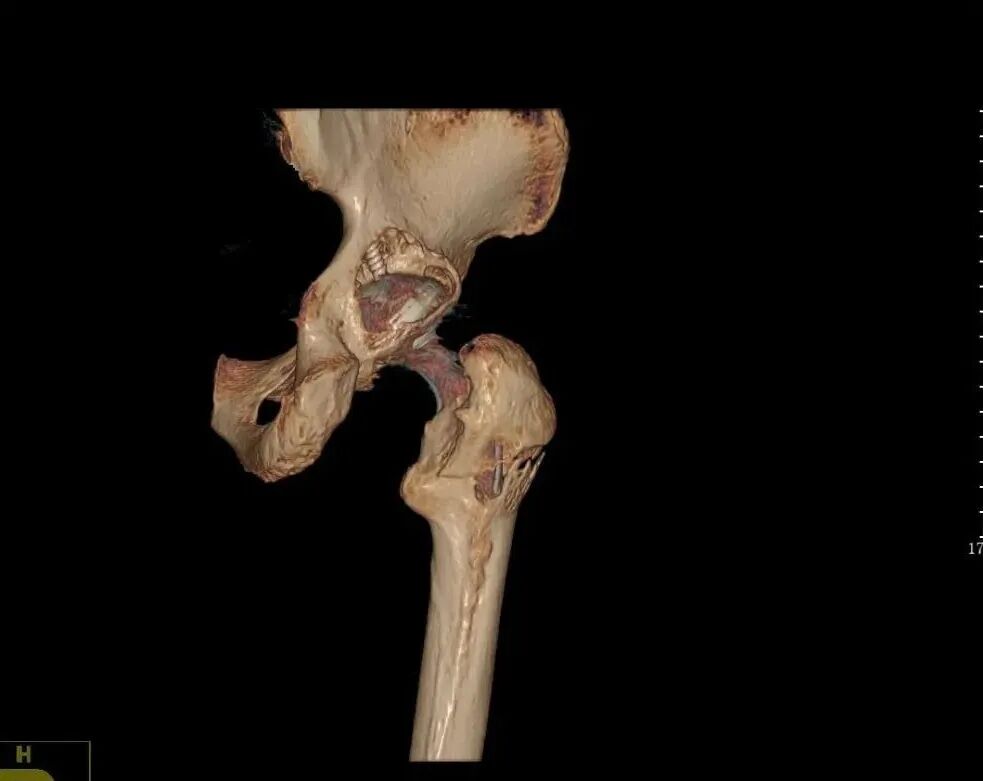

▲术前

检查发现其右侧髋臼后壁、后柱及股骨大粗隆存在明显骨溶解,常规假体无法满足手术需求。且患者高龄、基础疾病多,髋关节的重建是一个非常大的挑战!